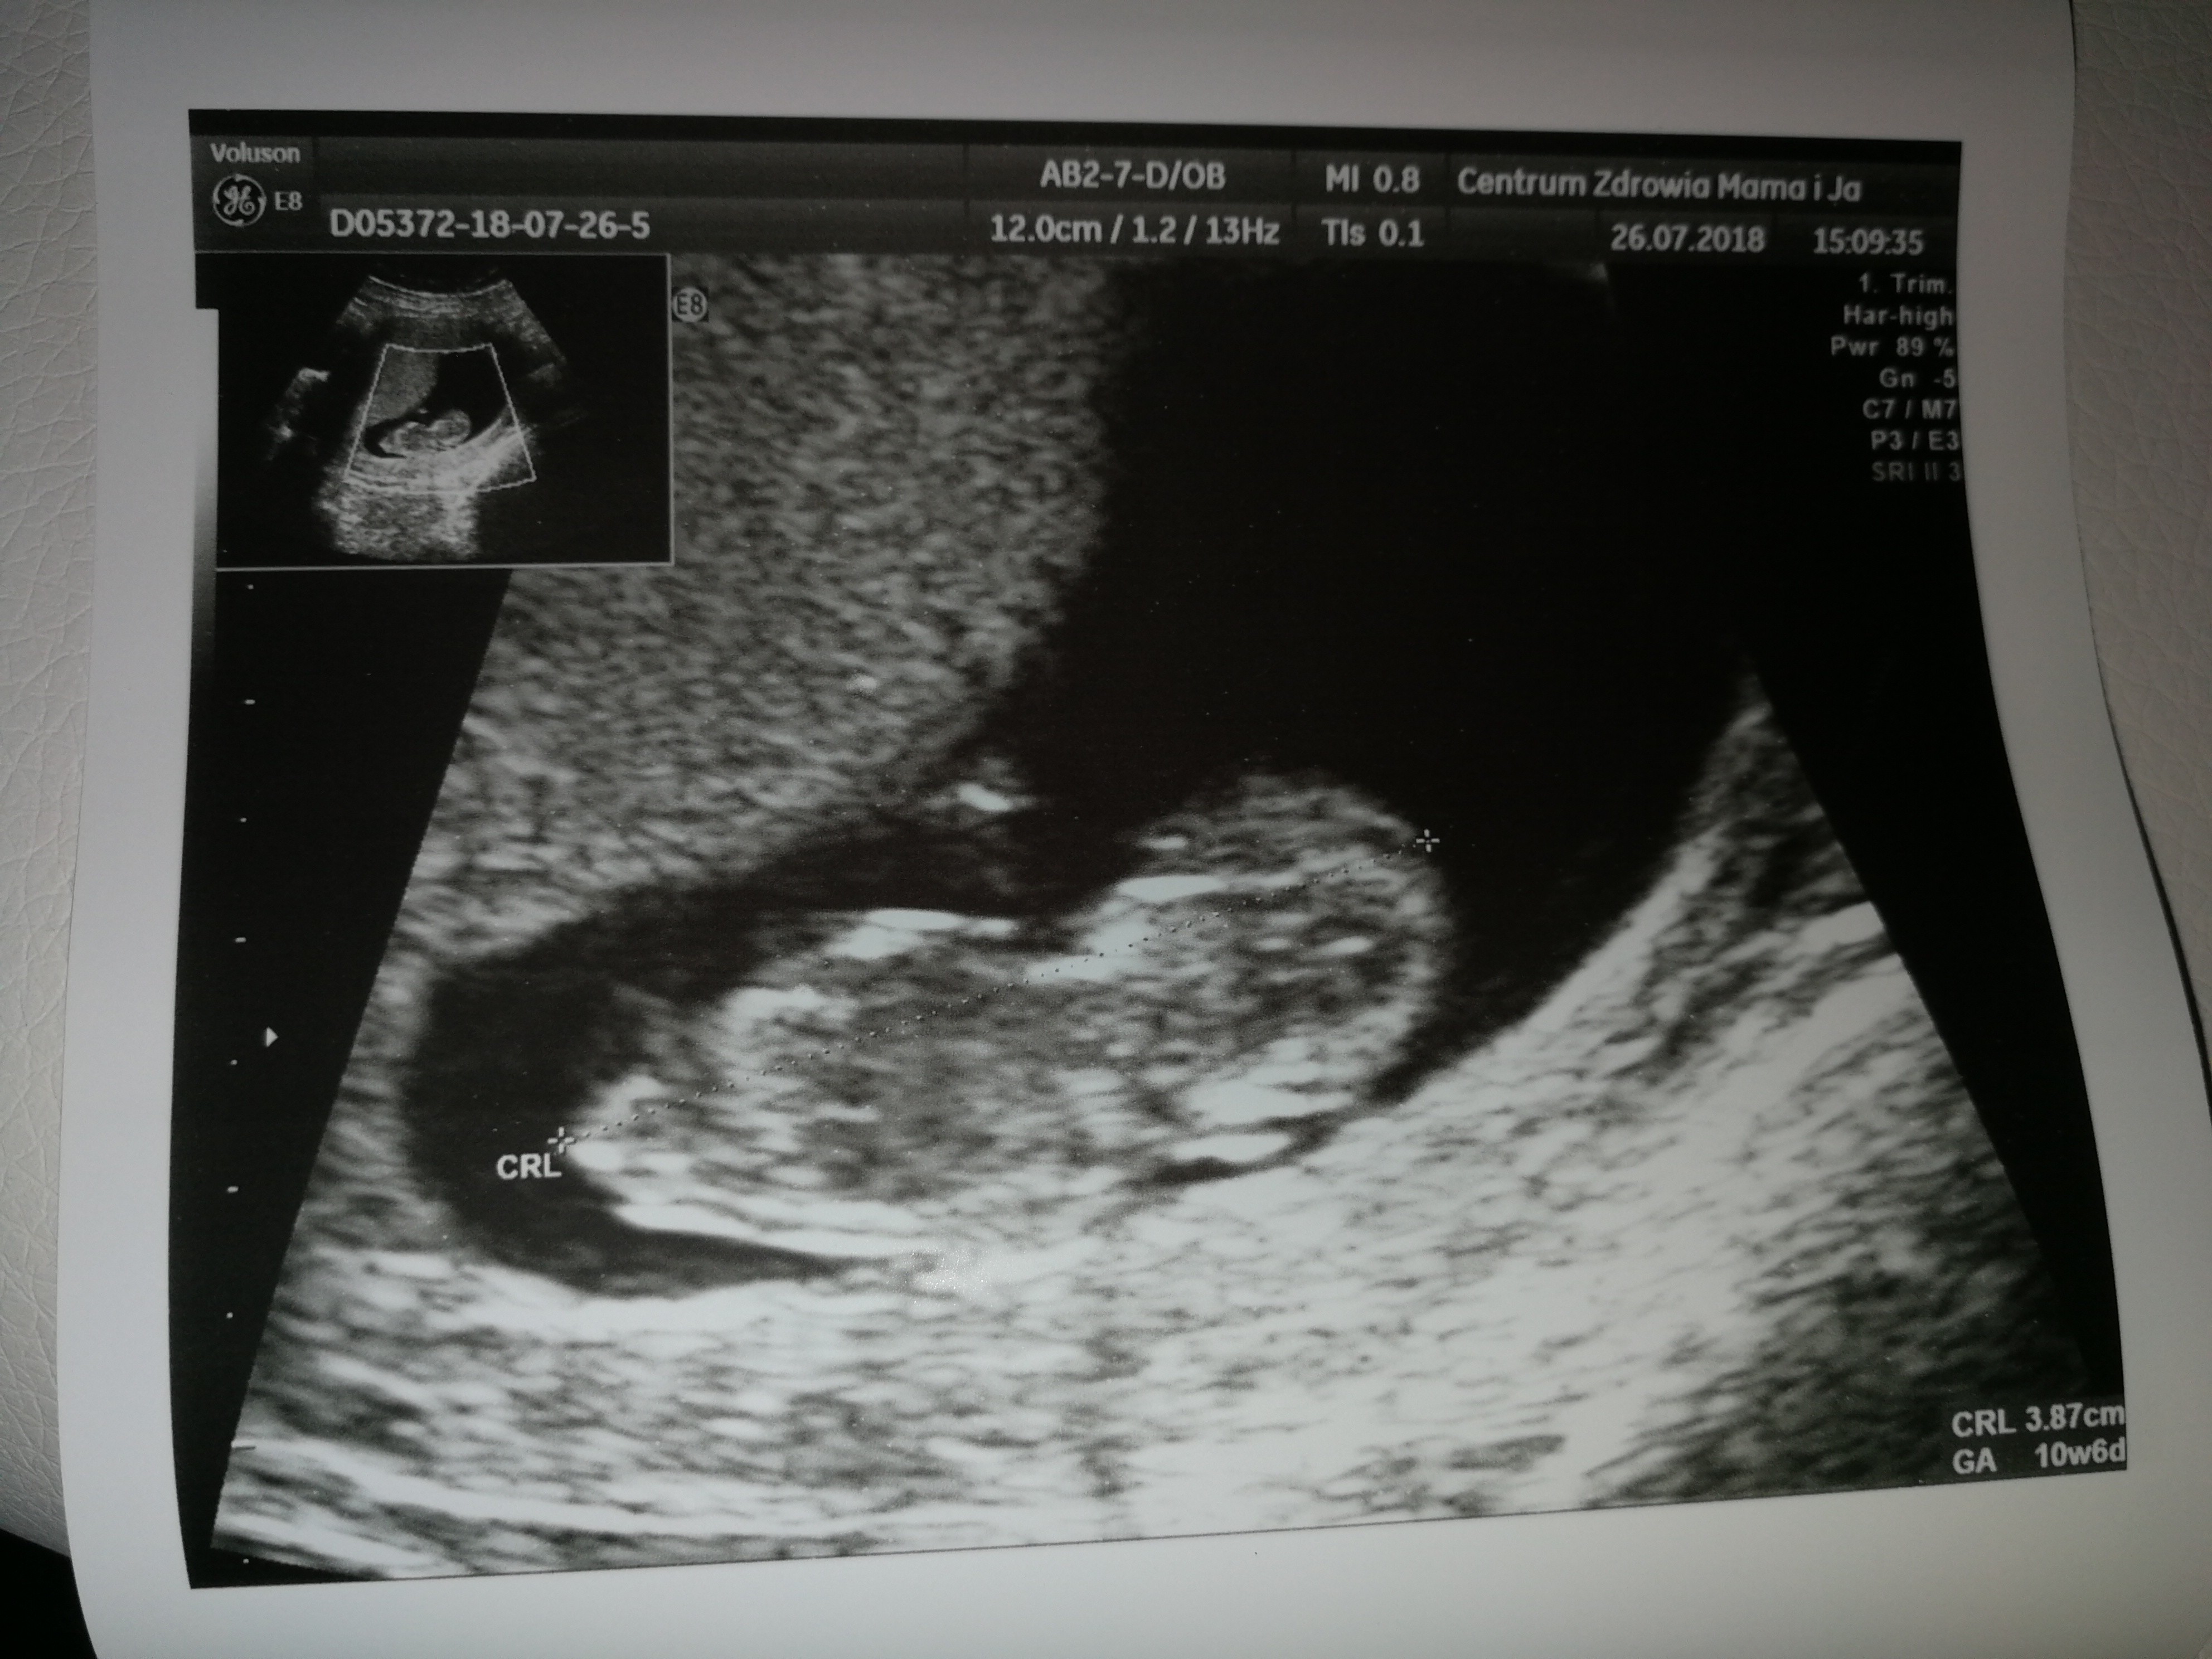

Poszłam więc dzisiaj prywatnie i bez problemu dostałam l4 i od razu zrobił mi lekarz na szybko usg już przez brzuch i tu moje pytanie bo dziś 10t i 6d i czy dzidziuś nie jest za mały - 3.87cm a serduszko 171.